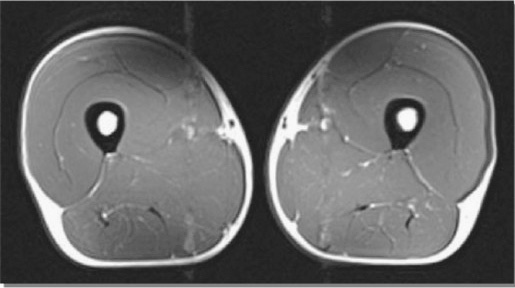

Xin cảm ơn sự đồng ý của tạp chí Physician and Sportsmedicine, Berwyn, PA cho phép tái xuất bản các hình ảnh trên trang này từ bài viết “Tập luyện kéo dài giúp duy trì khối lượng cơ bắp ở các vận động viên lớn tuổi” của tác giả Wroblewski A.P. (đồng tác giả chính), Amati (đồng tác giả chính), Smiley M.A., Goodpaster B., Wright V. từ tạp chí Physician and Sportsmedicine, 2011. Sử dụng với sự cho phép của tạp chí Physician and Sportsmedicine, Berwyn, PA.